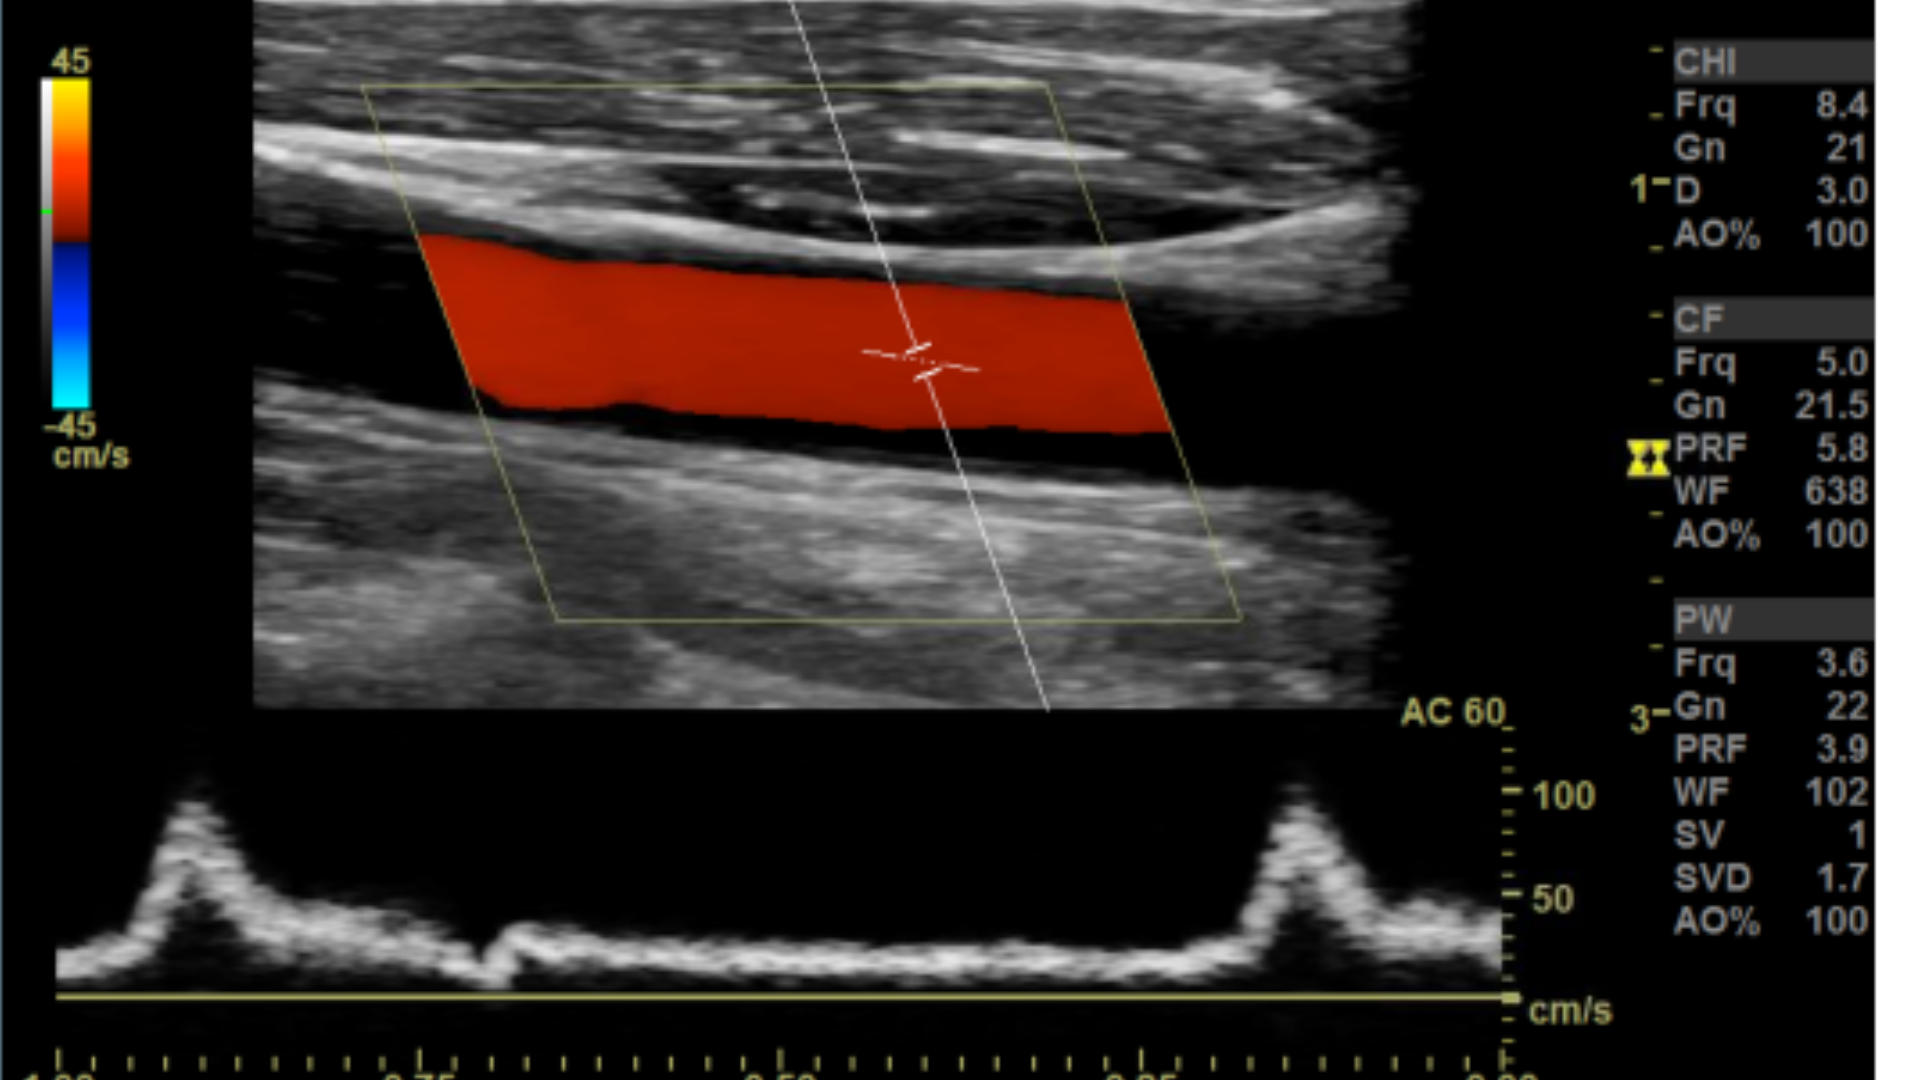

Taking technically superior images not only looks aesthetically pleasing, it is important in that it provides accurate data to render a correct diagnosis. A few parameters you may want to tweak are the doppler scale or pulse repetition frequency PRF and gain for both color and spectral doppler.

Optimal Doppler settings

Other parameters to consider are sweep speed, wall filters, color box size and orientation, sample box size and whether you’re color scale is inverted to name a few.